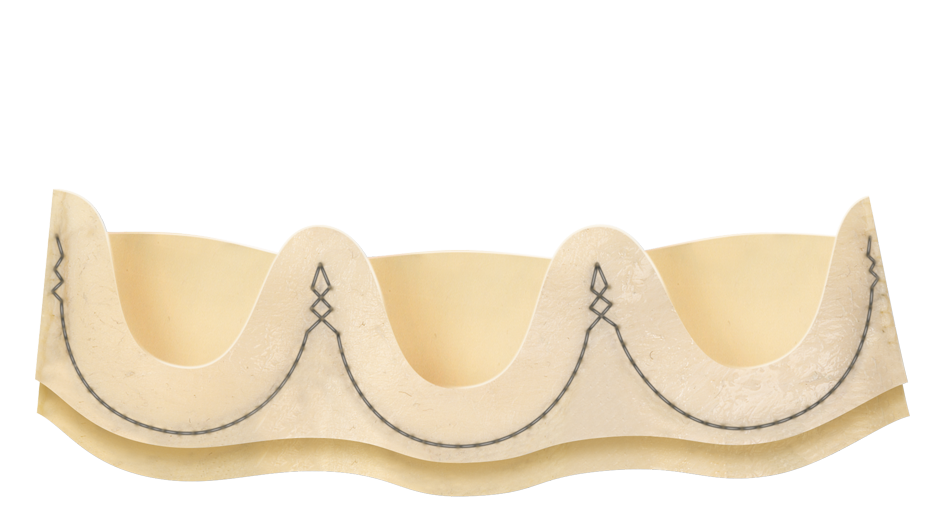

Double sheet design

An outer sheet acts as a cushion that minimizes stress transferred to the leaflets.

Fully atraumatic collapsing

The collapsing procedure does not affect the leaflets preventing any possible damage to the tissue.8

Perceval Plus leaflets remain open when a TAVI is deployed inside it. The sinusoidal struts and the open leaflets create a space between the coronary ostia and the leaflets themselves wich is preserved even after the TAVI deployment.

Minimized risk of sinus sequestration

By design, the Perceval Plus leaflets, when open, do not touch the STJ, thus avoiding sinus sequestration.